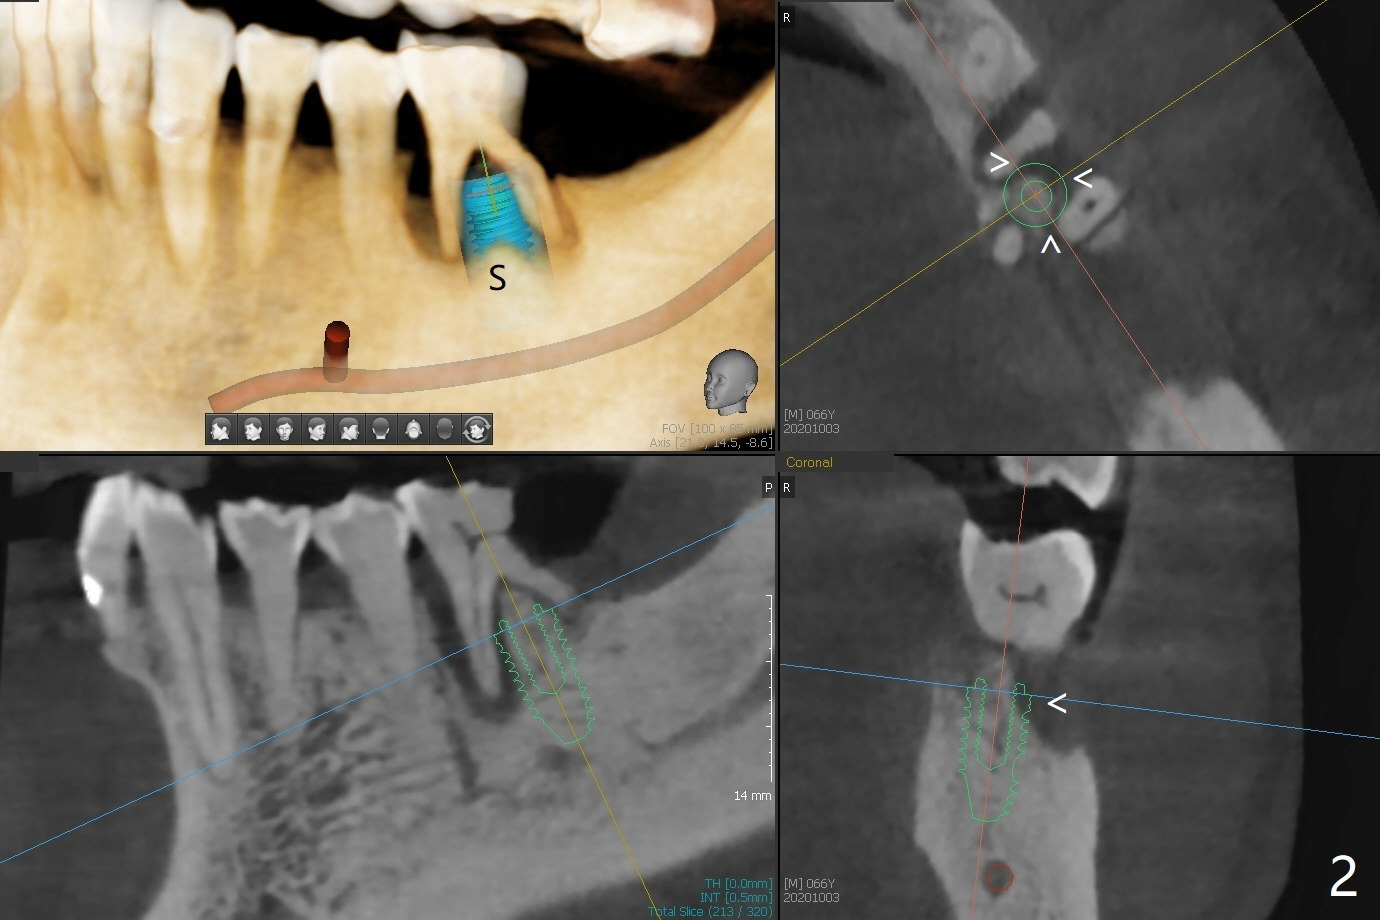

66岁男要求拔除左下6(图一),中隔好像斜型吸收(S),如果即刻植牙植入中隔,冠方螺纹三面暴露(图二:箭头)。当植入近中牙槽窝(图三:M),似乎只有一面螺纹暴露。病人右下3,4颊侧骨板仿佛植骨后修复,不妨尝试同样方法。不过需要如下改善:尽量少制备粘性骨块,用剩余PRF上清液临时调袢骨粉,放置牙槽窝底部(好压紧),而粘性骨块放在颊侧缺陷和牙槽窝开口(防止下面骨粉脱落),最后放置PRF膜。安置间隙维持器,拍摄根尖片,放置牙周敷料(避免缝线)。